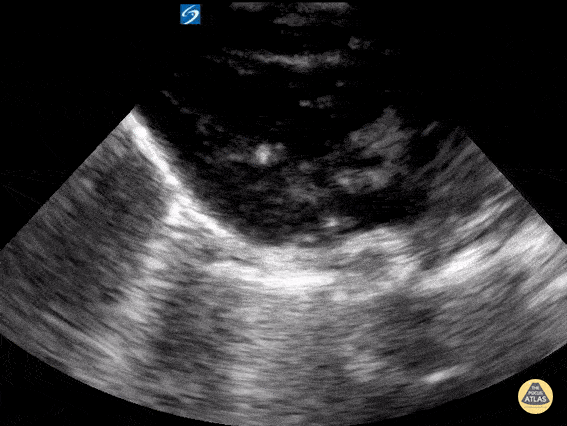

Toddler presenting in asystolic cardiac arrest. PSLX view demonstrating asystole with complete absence of cardiac movement. Contributor: Matthew Moake, MD PhD